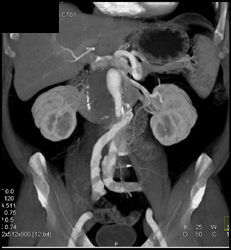

Diagnosis

Ulceration W/o Abscess